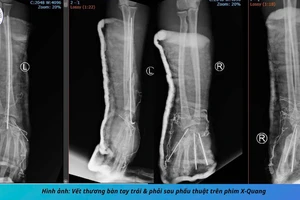

Quảng Nam: Dập nát 2 bàn tay do pháo nổ